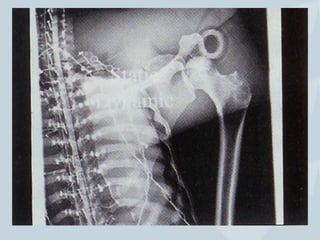

Unstable ACJ

10